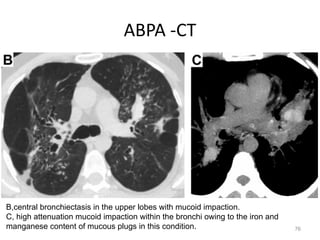

ABPA -CT

B,central bronchiectasis in the upper lobes with mucoid impaction.

C, high attenuation mucoid impaction within the bronchi owing to the iron and

manganese content of mucous plugs in this condition.